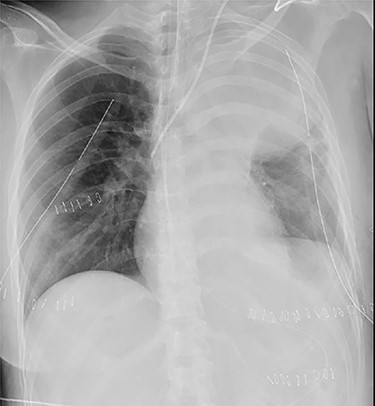

A 38-year-old woman with schizophrenia committed suicide by a self-infliction of sharp force into the chest and abdomen. She presented to our hospital in a critical condition. On arrival in the emergency room (ER), she developed hemorrhagic shock, which leads to an emergent abdominal damage control surgery under general anesthesia. She lost cardiac activity in the operating room during exploratory laparotomy. A left-sided basal thoracostomy, cross-clamping of the descending thoracic aorta, and open cardiac massage were also performed. She received gauze packing at the bleeding point and temporarily close the abdomen and chest wall. After the surgery, she was transferred to the intensive care unit with mechanical ventilation and recovered from hemorrhagic shock. Two days later, a second-look laparotomy was performed. ER doctors verified the hemostasis and closed the patient’s abdomen and chest. On the same day, a chest radiograph revealed pulmonary atelectasis of the left upper lobe (Fig. 1). Computed tomography (CT) revealed alveolar bleeding, pneumonia and atelectasis of the left upper lobe (Fig. 2). Despite antibiotic therapy and repeated endobronchial sputum aspiration, radiologic findings were not improved. On the seventh postoperative day, she was referred to our department for suspected lung abscess. When compared to the chest CT images on the day of initial surgery, pulmonary torsion was suggested (Fig. 3A). The sagittal CT images were reconstructed, and the torsion of the left upper lung lobe was diagnosed (Fig. 3B). Therefore, an emergency left upper lobectomy was performed through a left thoracotomy. Intraoperatively, the left upper lung lobe was rotated clockwise and was hemorrhagically and congestive infarcted. Due to severe pulmonary congestion, it was difficult to obtain the surgical field of view. The pericardial sac was opened and the intrapericardial isolation of the left upper pulmonary vein was performed. To prevent separation of the thrombus and necrotic material in the left upper lobe, we first dissected the left upper pulmonary vein before resolving the torsion and performing the lobectomy. She had a complete pulmonary fissure. Moreover, only one first pulmonary artery branch had ruled the approximately pulmonary arterial flow of her left upper lobe. The left upper lobectomy was performed. The patient made an uneventful recovery.

Axial (A) and sagittal (B) computed tomography images few hours after initial emergency operation.